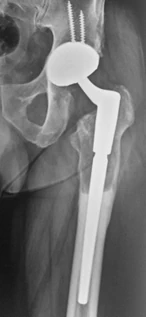

A tale proposito ho sviluppato in collaborazione con Medacta, nota e azienda Svizzera molto attiva in campo ortopedico e aperta alle innovazioni tecnologiche, un nuovo impianto specifico per la chirurgia di revisione acetabolare progettato per affrontare i casi più complessi di difetto osseo sfruttando per la stabilità meccanica l’osso iliaco.

Caratteristiche distintive del cotile Mpact Ilac Screw e perché viene scelto in casi difficili:

1. Design e Modularità

È un sistema non cementato che punta sulla stabilità meccanica immediata e sulla rigenerazione biologica a lungo termine:

- Forma emisferica: consente la correzione di inclinazione ed antiversione

- Vite Polare: è l’innovazione tecnologica peculiare che consente di massimizzare la stabilità primaria ancorandosi saldamente entro l’osso iliaco solitamente presente anche nei casi più gravi di difetto osseo.

3. Stabilità iliaca

- Concetto vecchio, disegno moderna: La vite iliaca funge da vero e proprio “pilastro”, trasferendo il carico meccanico direttamente nella colonna posteriore/superiore del bacino, entro l’osso iliaco, bypassando le zone di osteolisi e il difetto cavitario/segmentario dell’acetabolo.

In sintesi, il cotile Mpact Ilac Screw è un cotile innovativo che permette di “ricostruire” l’articolazione anche in presenza di ampi difetti ossei evitando il ricorso a protesi custom-made o altri impianti molto più complessi e costosi.